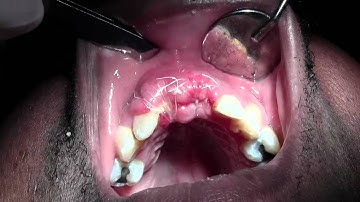

Bone Grafting #5 Site with Mineross/Cytoplast d-PTFE, 2 Week Post-op